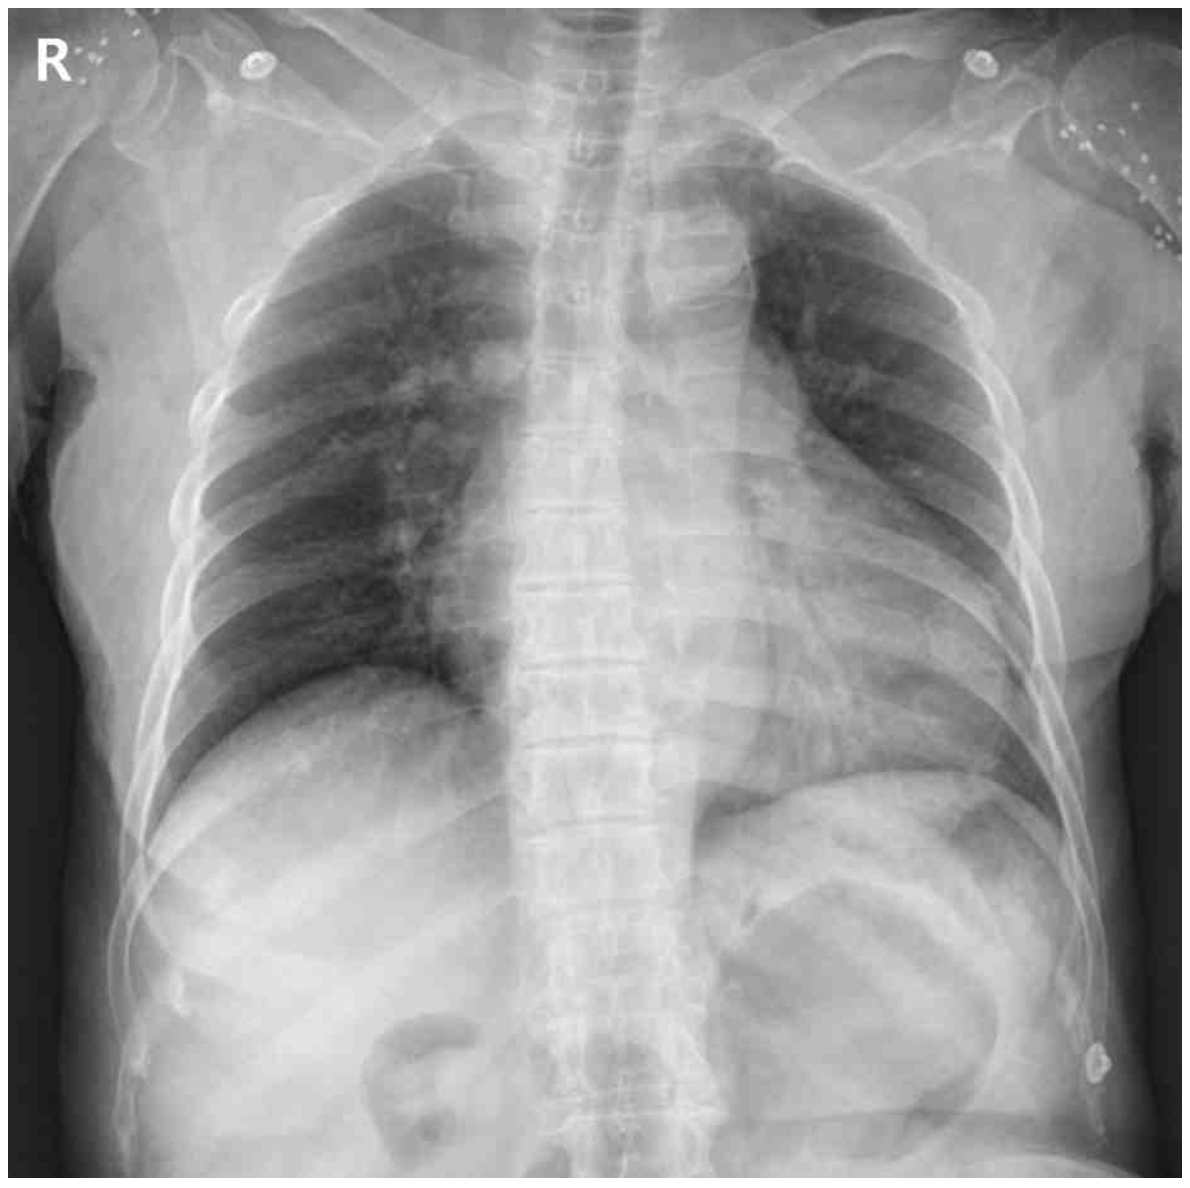

66세 여자가 1주 전부터 기운이 없고 숨이 차서 병원에 왔다. 2년 전부터 말기신장병으로 혈액투석 중이다. 혈압 90/68 mmHg, 맥박 145회/분, 호흡 24회/분, 체온 36.1℃이다. 숨을 들이쉬면 수축기 혈압이 63 mmHg으로 낮아진다. 심음은 저하되고 호흡음에는 이상이 없다. 가슴 X선사진과 심전도이다. 혈액검사 결과는 다음과 같다. 진단은?

CXR: Cardiomegaly

• CXR 상 cardiomegaly가 확인되며 혈액검사 상 BNP가 증가했으므로 호흡곤란의 원인은 심장성이다.

CXR: Water-bottle appearance